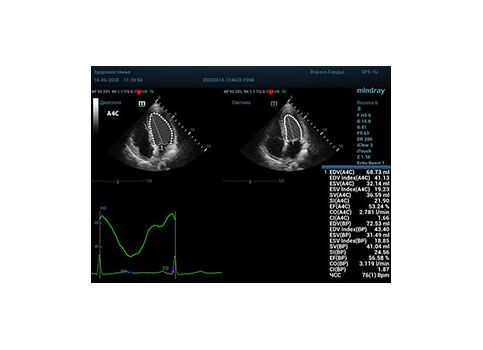

ИИ использует различные методы для анализа ЭхоКГ и определения ФВ․ Один из распространенных подходов – это сегментация левого желудочка․ Алгоритм автоматически выделяет контуры левого желудочка на ЭхоКГ-изображении в фазе систолы (сокращения) и диастолы (расслабления)․ Затем, на основе этих контуров, вычисляется объем желудочка в обеих фазах, и, наконец, определяется ФВ․

Например, существуют системы, которые могут автоматически анализировать ЭхоКГ-изображения и генерировать отчеты, содержащие информацию о фракции выброса, размерах полостей сердца и других важных параметрах․ Эти отчеты помогают врачам быстрее и точнее оценивать состояние сердца пациента․